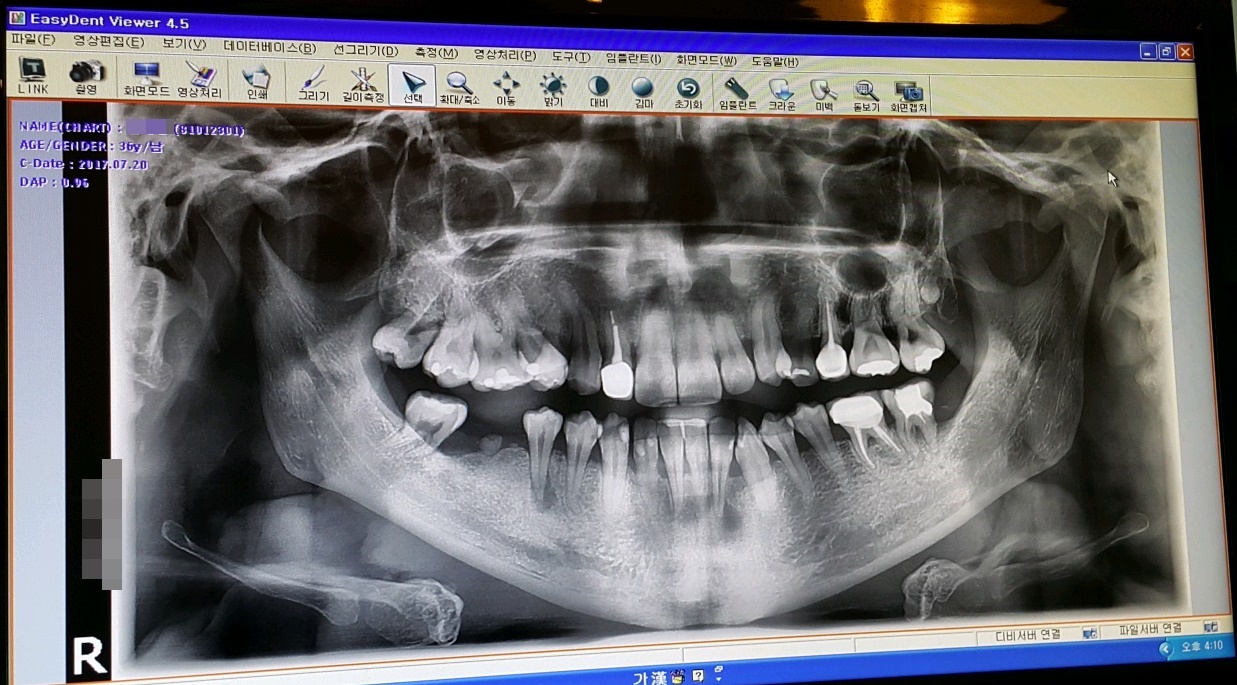

3년전 부정교합 시작하기 전의 내 치아 상태는 지금 생각해 보면 정말 최악?? 이였다..

썩은치아와, 부정교합으로 인해 삐뚤어진 치아들...

교정때문에 발치했던 치아포함 임플란트를 해야할 날이 다가왔다...

해서 임플란트 포함 치료할 치아들 견적 상담 받은 결과...

오른쪽 아래 어금니는 양쪽으로 받혀주는 치아들도 없는상태에 보철기가 당겨주는 역할까지 하는 바람에

뿌리쪽이 곧 뽑아야 할 만큼 너무 많이 빠져나와서 어쩔수 없이 제거하고 임플란트까지 하기로 했다.